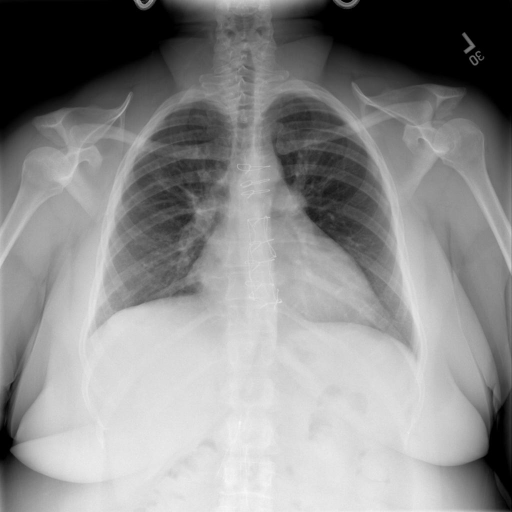

|X光影像|诊疗报告(医生)|XrayGLM|

|:-|:-|:-|

||根据X射线图像,心脏大小正常,肺部看起来很清晰。已经排除了肺炎、积液、水肿、气胸、腺病、结节或肿块的存在。该发现表明一切正常。换句话说,总体印象是胸部正常。|X光片显示,心脏大小正常。肺部没有气胸或胸腔积液的证据。骨骼结构看起来没有任何异常。总的来说,X光片表明没有发现急性心肺疾病的迹象。|